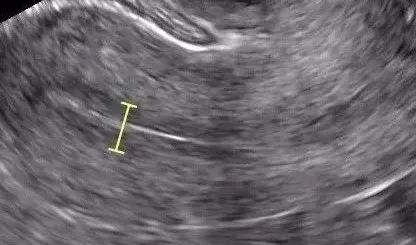

超声所见:

增生早期:月经干净的1-3天,子宫内膜相对比较薄,大概只有4-6mm。

增生中期:子宫内膜开始增长,内膜逐渐增厚,约8-10mm。

增生后期:子宫内膜调整,厚度有9-10mm。

内膜由于受到孕激素的作用,子宫内膜腺体变长,子宫内膜厚度不变,呈现锯齿状。一般为10-14mm。

内膜在不同时期的正常值不同,但如果内膜增生晚期到分泌期≤7mm,增生早期≤4mm便认为是子宫内膜薄。

也就是说假定月经周期是28天,到第14天排卵期,子宫内膜应该是最厚的,如果子宫内膜厚度还达不到7mm就认定内膜薄。

也有产后、流产后,或者宫腔手术后子宫内膜薄,甚或子宫内膜粘连,超声所见内膜薄厚不一,回声不均。瘀血未清,留滞宫腔,瘀阻胞宫,血行不畅而量少,色紫黑有块,小腹刺痛拒按。